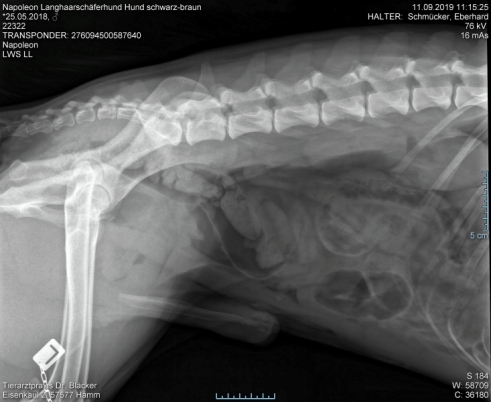

Röntgentermin am 11.09.2019

Hier sind  HD-ED Aufnahmen von unseren “Napoleon von KaTum”   alles Top

Keine HD und kein ED,LÜW ist alles gut